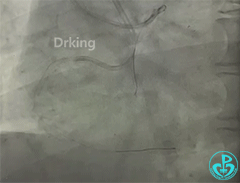

左冠造影:

导丝怎么扩收藏:器械难以通过的CTO病变之技术图谱_https://www.jmylbn.com_新闻资讯_第2张

导丝怎么扩收藏:器械难以通过的CTO病变之技术图谱_https://www.jmylbn.com_新闻资讯_第3张

导丝怎么扩收藏:器械难以通过的CTO病变之技术图谱_https://www.jmylbn.com_新闻资讯_第4张

导丝怎么扩收藏:器械难以通过的CTO病变之技术图谱_https://www.jmylbn.com_新闻资讯_第5张